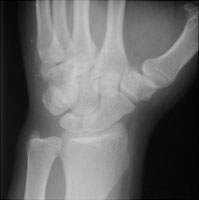

- Click on the image for a larger versionALateral radiograph of the wrist. This shows a bony fragment at the carpometacarpal region.